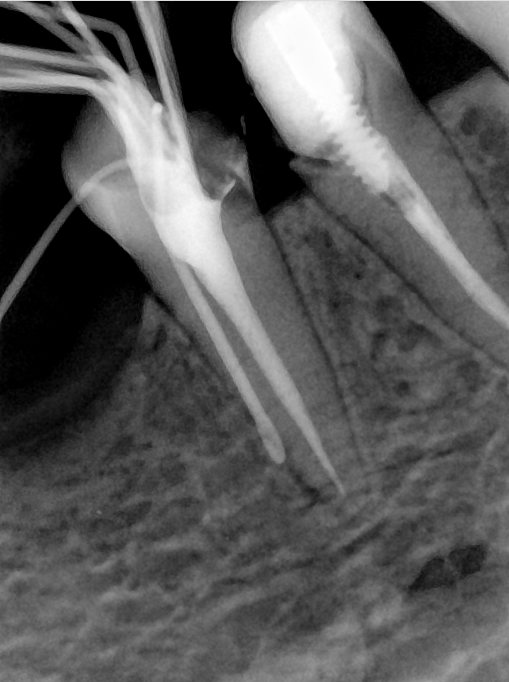

CR/DR 牙齿分割阶段记录

当前进展

- 完成了 CR/DR 牙齿相关分割训练

- 当前结果已经达到阶段预期,但仍有细节问题需要继续处理

相关测试

遇到的问题

- 训练过程中出现过 mask 下移问题

- 部分结果会出现 box 填充异常

- mask 边缘仍然有比较明显的锯齿感

参考

第二版算法问题测试

Updated: 2026-04-13(更新日期)

| 第一版 | 第二版 | 是否解决 | |

|---|---|---|---|

![]() | ![]() ![]() 边角识别有问题 龋齿识别不全 牙髓识别不全 | ![]() | 解决 |

![]() | ![]() 边角识别有问题 识别信息有误 自查(牙冠识别不全) | ![]() | 解决 |

![]() | ![]() ![]() 边角识别有误 大范围填充识别遗漏 | ![]() | 解决 |

![]() | ![]() 识别信息不全 | ![]() | 解决 |

![]() | ![]() ![]() 边角问题 牙胶识别不全 牙冠识别不全 | ![]() | 解决 |

![]() 换图片 | ![]() | ![]() 牙冠部分稍微白了一些就识别成小范围修补,部分判断异常 | 部分解决,修复类略敏感,牙冠部分稍微白了一些就识别成小范围修补,部分判断异常。 |

![]() | ![]() ![]() 牙冠识别不全 牙髓不全 根尖炎龋齿识别有误 | ![]() | 解决 |

![]() | ![]() | ![]() | 解决 |

![]() 换图片 | ![]() | ![]() | 解决 |

![]() | ![]() 牙冠识别有误 | ![]() | 解决 |

![]() 换图片 | ![]() ![]() 边角识别有误 | ![]() 修复类敏感 | 部分解决,图像过白,导致修复类判断异常。 |

![]() 换图片 | ![]() 牙冠识别不全 | ![]() 修复类敏感 | 部分解决,图像过白,导致修复类判断异常 |

结论:修复类出现了不鲁棒的情况,后续需要加入轮廓的扩充数据进行增强。